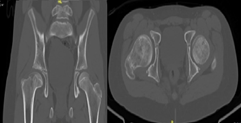

A 12-year-old male patient, who began medical controls in our service in 2018, diagnosed with Legg-Calvé-Perthes disease of the right hip (Figure 1), presenting pain when standing, agitated gait, and claudication. In 2022 in tomographic control (Figure 2) and CT with 3D reconstruction (Figure 3) that evidence right coxa magna and alteration of the femoral sphericity with CAM type morphology, associated with pain and limitation of range of motion, was the reason for which it was decided to perform surgical intervention. Physical exam: Pain and limitation of range of motion (right/left flexion 100°/100°, right/left internal rotation 28°/45°, right/left external rotation 12°/20°, limited abduction due to pain in the right lower extremity).

Figure 2 Computed Axial Tomography of the hip from the year 2022, showing evidence of the right coxa magna and alteration of the femoral sphericity of CAM type morphology.

2. Computed Axial Tomography of the hip from the year 2022, showing evidence of the right coxa magna and alteration of the femoral sphericity of CAM type morphology.